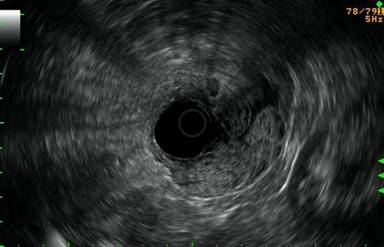

A 67-year-old woman with a body mass index of 40 Kg/m2 was admitted to our hospital complaining of acute upper gastrointestinal bleeding. She had experienced a syncope episode followed by melenas. An upper digestive endoscopy revealed a large friable polypoid mass about 5 cm in diameter, surrounding 3/4 of the internal lumen, coming from the 3rd portion of the duodenum, about 3 cm distal to the ampulla (Figure 1). There were no other polypoid lesions in the duodenum. Multiple endoscopic biopsies (five samples) confirmed a villous adenomatous polyp with mild-moderate dysplasia. Abdominal CT showed the mass to be confined to the duodenum. An extension study was completed via endoscopic ultrasonography which showed no disruption of any of the muscle layers of the duodenum (Figure 2) and no penetration into the pancreas. The pancreatic duct was preserved and there were no pathological regional lymph nodes. Tumor markers (CEA and CA 19-9) were negative. From the day of admission to the day of the surgery, the patient required transfusion of 7 units of red blood cells.

Figure 2. Endoscopic ultrasonography revealing the depth of invasion of the tumor into the muscular layers. The serosa was respected. |